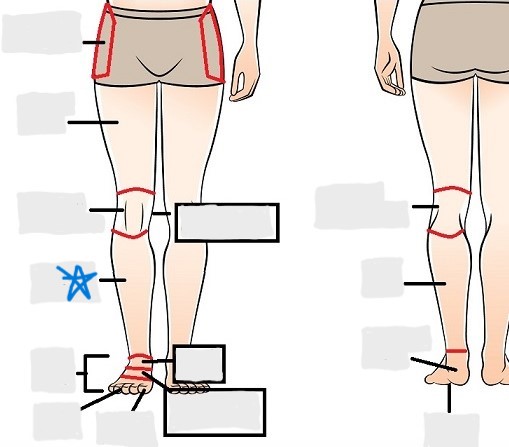

axial

appendicular

coxal

femoral

patellar

popliteal

crural

sural

peroneal

calcaneal

plantar